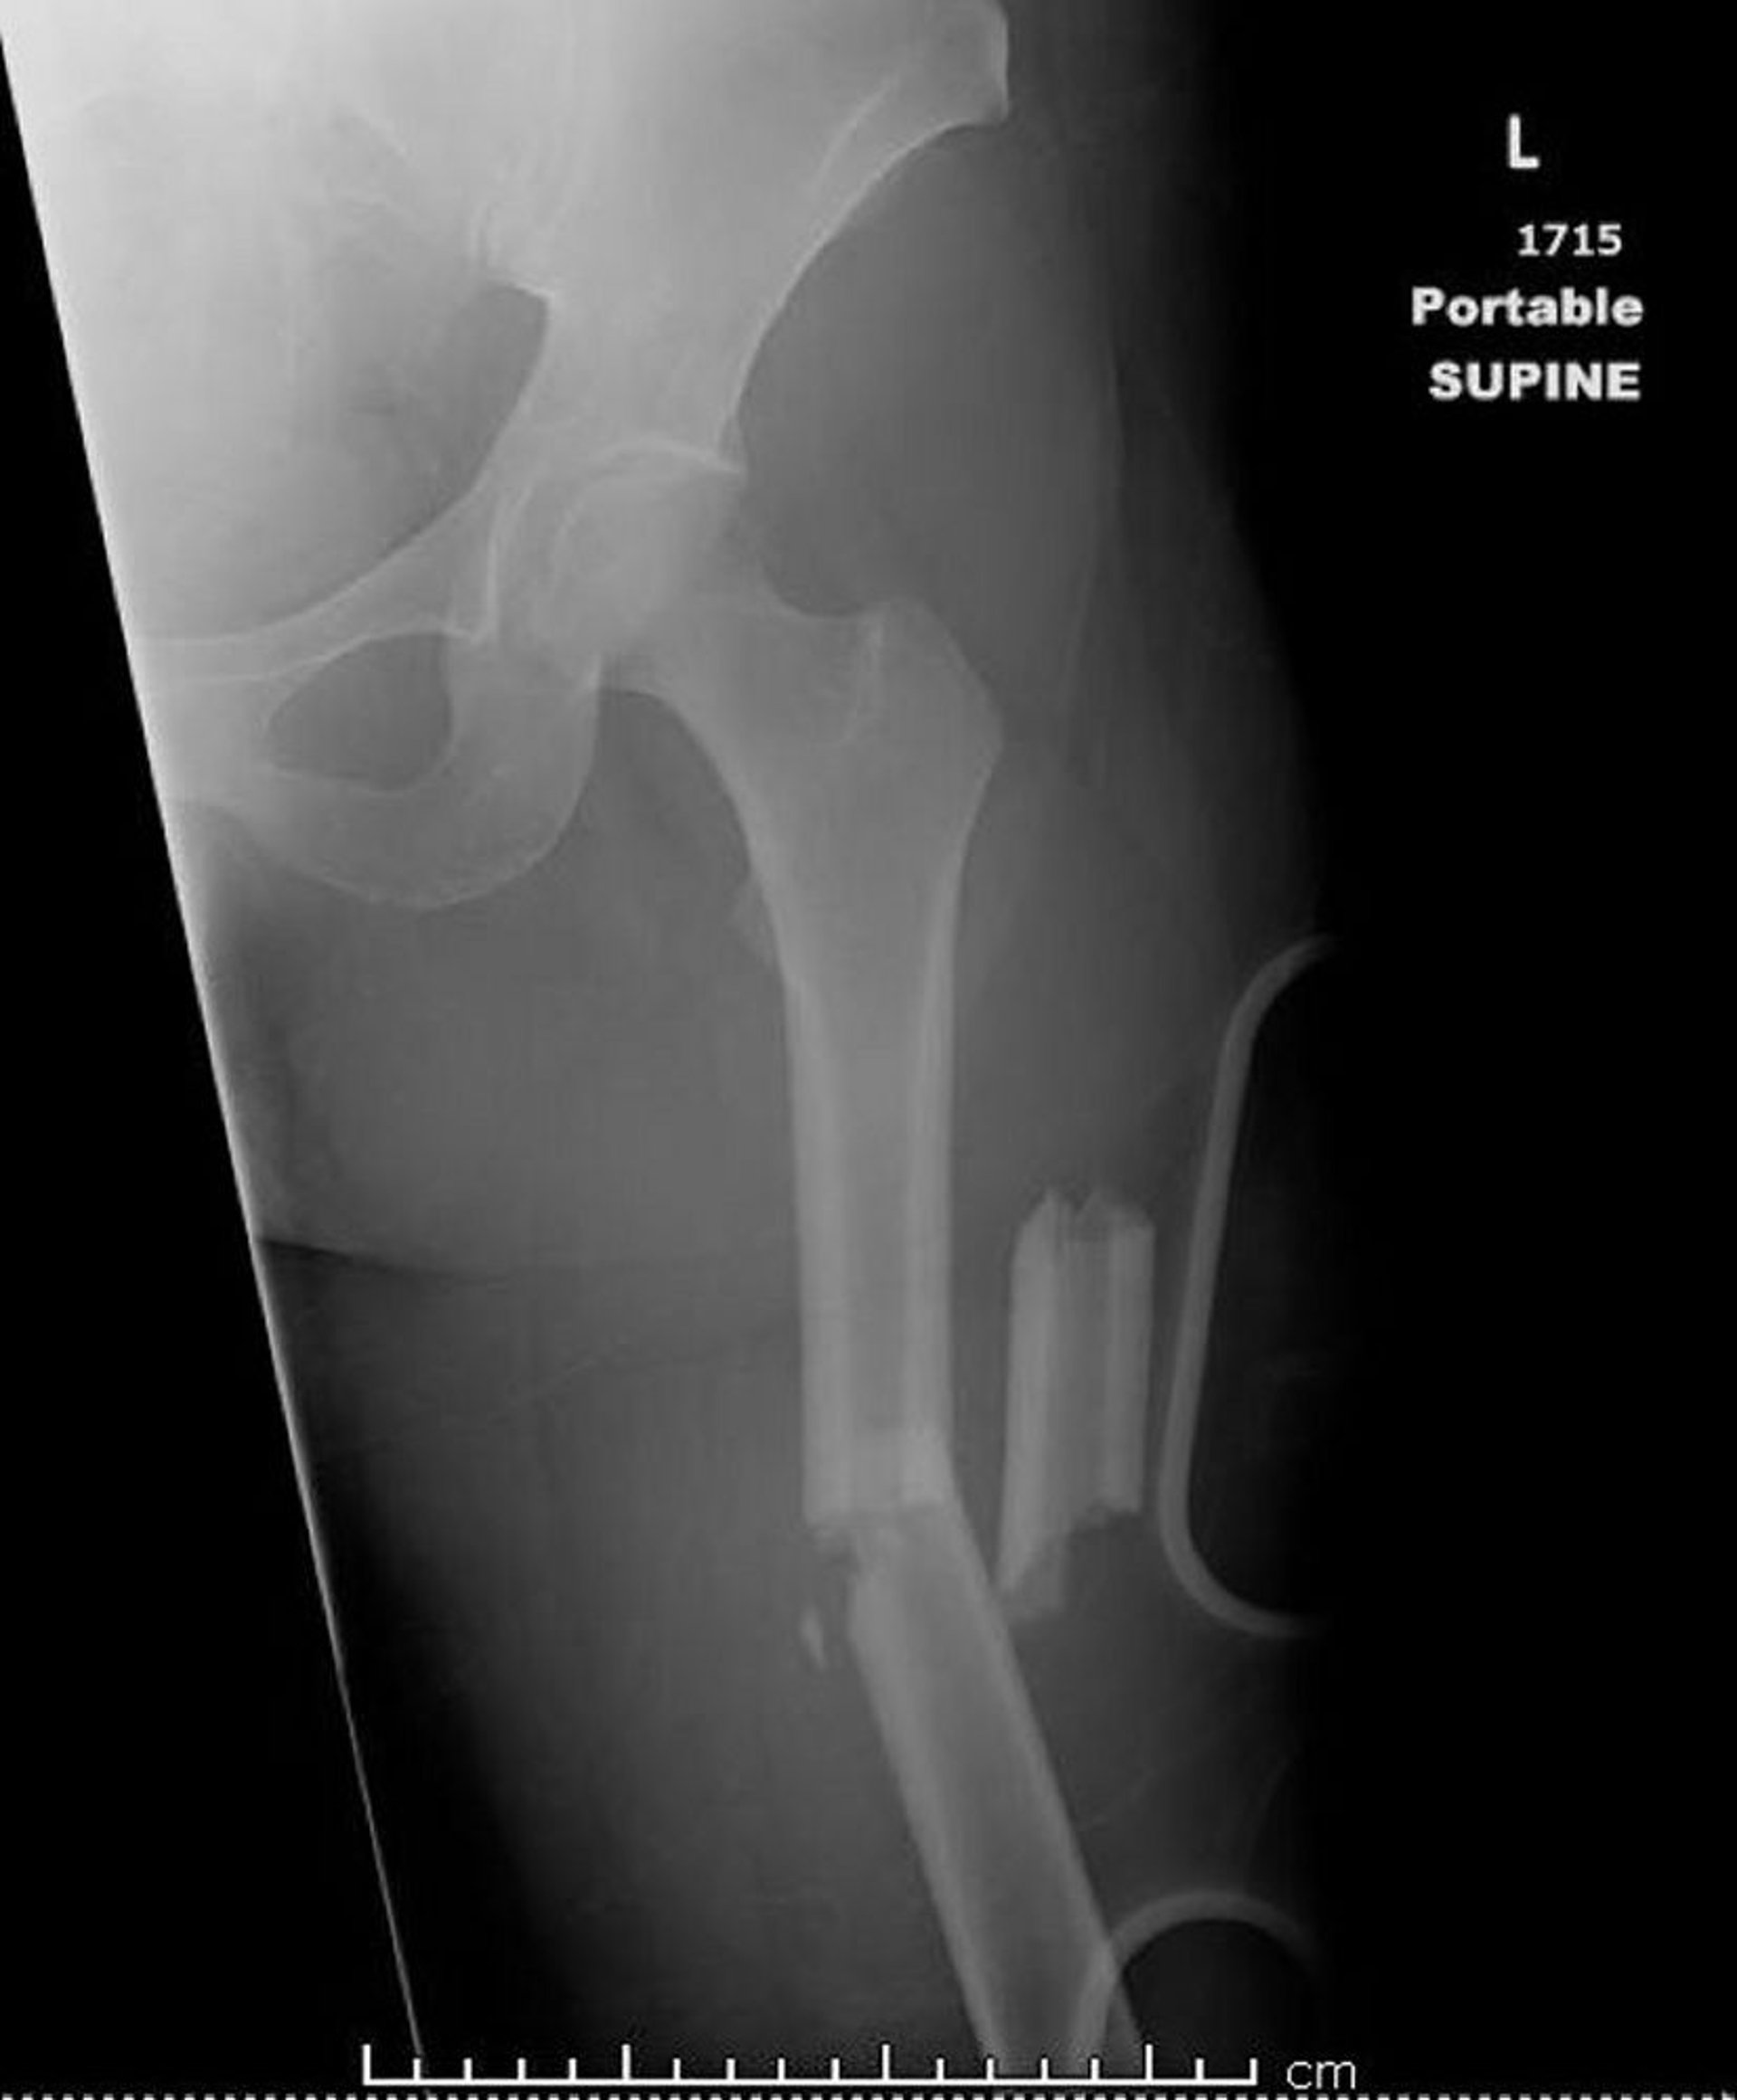

Gãy xương đùi ở phần giữa thân xương (1)

Hình ảnh này cho thấy một chỗ gãy ở phần giữa thân xương đùi, gãy vụn, gập góc và xương bị ngắn lại.

Hình ảnh do bác sĩ Danielle Campagne cung cấp.